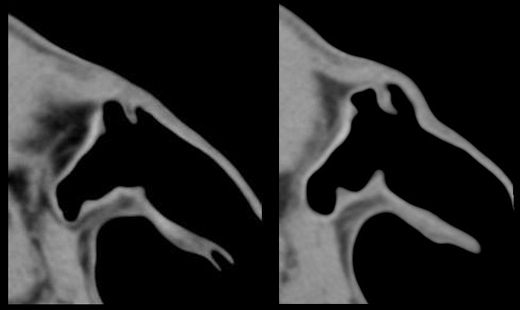

Le cartilage de l’oreille externe donne parfois lieu à toutes sortes d’animaginations en tomodensitométrie. Notre ami Julien Olive, radiologue à CHV St-Martin en France et récemment diplômé d’une résidence en imagerie à la faculté de médecine vétérinaire de Saint-Hyacinthe, en a récemment vécu deux en scannant la tête d’un chien. On savait déjà qu’il imaginait des têtes chevalines un peu partout avant son séjour chez nous. Mais nous ignorions que l’orignal – où l’élan d’Amérique – était maintenant rentré dans sa tête ! Est-ce l’effet secondaire d’une overdose de poutine ?!